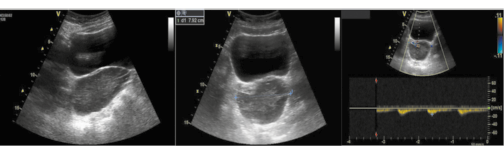

Все 24 (100%) ребенка, госпитализированные в стационар с подозрением на ППМ, характеризовались наличием косвенных признаков перекручивания по данным ректоабдоминального исследования и/или УЗИ, в том числе по результатам проведенного допплерометрического исследования сосудов и/или обнаружения симптома «пружинки» на амбулаторном этапе (рис. 1, 2), что вкупе с данными анамнеза и жалобами явилось причиной для ускоренного проведения оперативного лечения.

Рис. 2. Ультразвуковая картина при ППМ – «симптом пружинки». Пациентка Г., 8 лет: а – перекрут сосудистой ножки правого яичника в виде спирали, при цветовом допплеровском картировании определяется разнонаправленный кровоток; яичник увеличен в объеме, однако контуры и структура яичника не изменены, кровоток в строме сохранен; определяется небольшое скопление свободной жидкости. Пациентка В., 10 лет: б – трансабдоминальное продольное сканирование, перекрут сосудистой ножки кистозно-измененного левого яичника; в – в режиме импульсного допплера определяется высокорезистентный артериальный кровоток питающего сосуда.